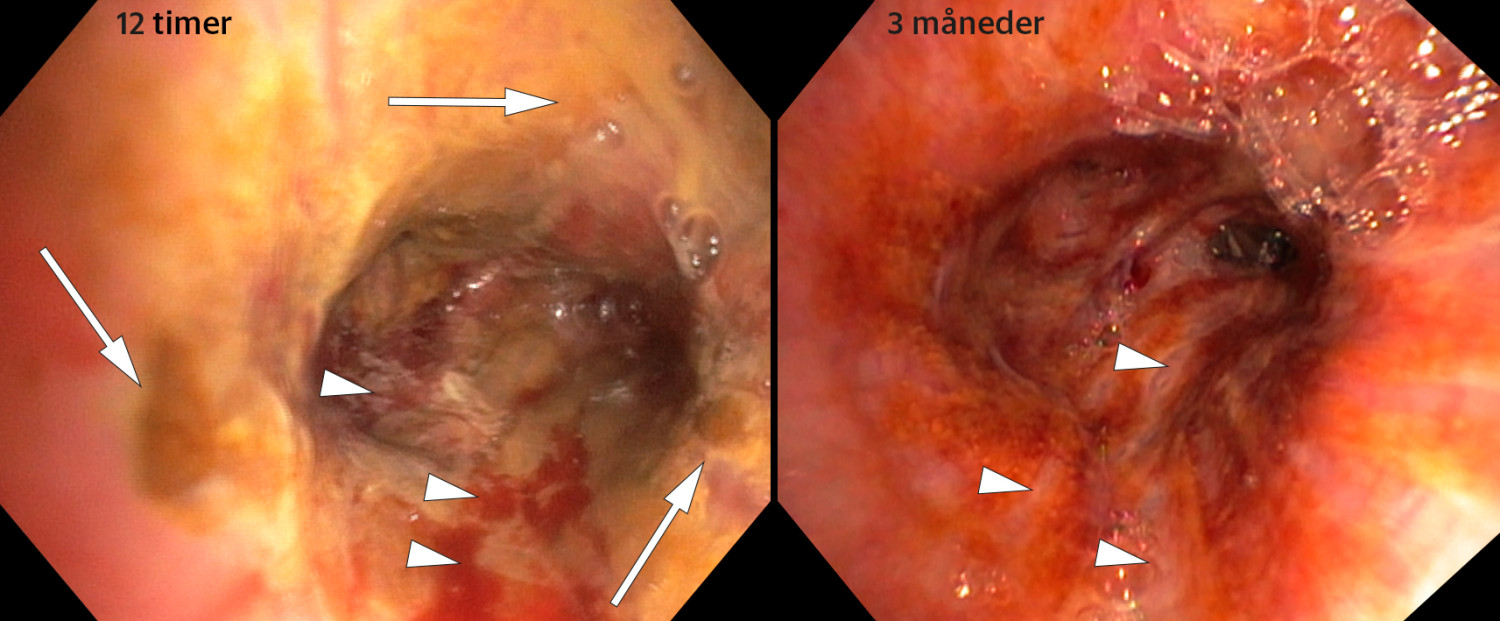

Bronkoskopi ble utført 12 timer etter uhellet (video). Det ble observert et brunlig ekspektorat på stemmebåndene. Fra carina, nedover høyre hovedbronkie og ved ostiet mot overlappen var det brunlig ekspektorat og belegg. Bronkialslimhinnen fremsto som inflammert. I bronchus intermedius var det uttalte forandringer (første bilde) med brunlig belegg (piler) og sårdanninger (pilhoder). Tablettene var gått i oppløsning, og det brunlige belegget lot seg ikke fjerne ved skylling. For å dempe inflammasjonen ble han satt på prednisolon frem til første kontroll tre uker senere. Ved kontroll etter tre måneder var han symptomfri, men det var fortsatt betydelige slimhinneforandringer (det andre bildet) med danning av arrvev (pilhoder).